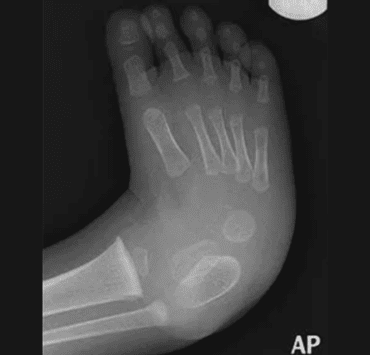

- Piciorul diabetic este definit prin prezenţa ulceraţiei, a infecţiei şi/sau a distrugerii ţesuturilor profunde, asociate cu probleme de ordin neurologic şi grade variate de boală vasculară periferică a membrului inferior. La fiecare 30 secunde, undeva pe glob este amputat un membru inferior din cauza diabetului!